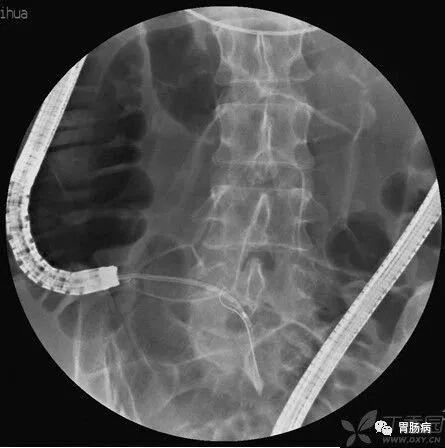

X线下,阑尾腔内注入造影剂显示阑尾腔的形态(椭圆形线圈),如有粪石(黑箭头),则行球囊取石术。并确认有无阑尾穿孔。